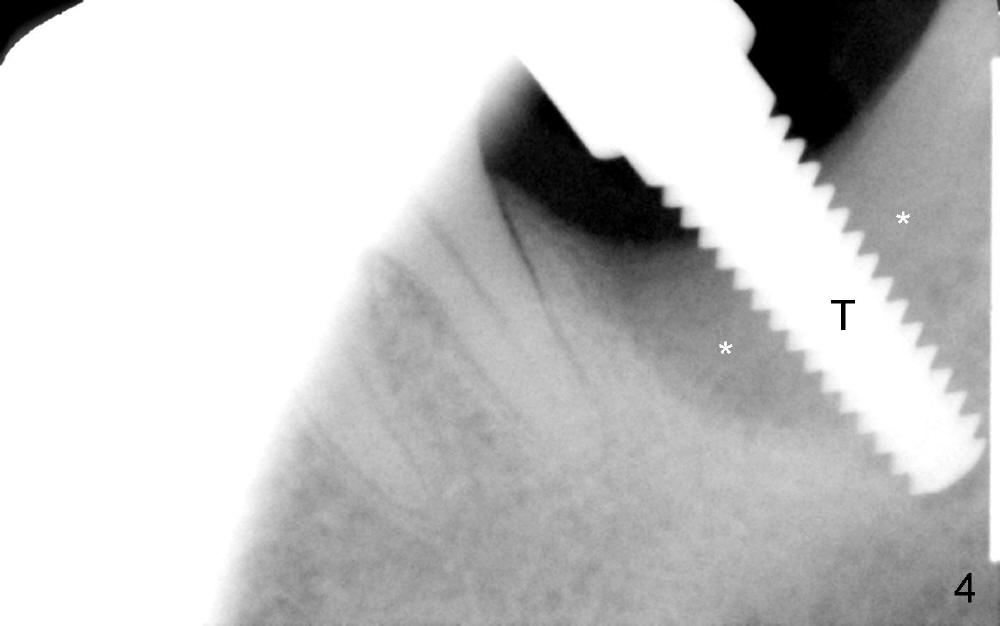

The lower left 2nd molar of a 45-year-old lady has perio-endo disease (Fig.1). The patient is not only very nervous, but also active in gag reflex. It is difficult to take good preop PA (Fig.1 *: ). Root canal therapy is performed. A relatively good PA is taken 1 year postop, again due to gap reflex (Fig.2). The tooth is still nonsalvageable (Fig.3). The last PA is taken 3.5 years before extraction and immediate implant. Infiltration anesthesia is administrated first. The patient experiences pain during early stage of osteotomy, but she does not report readily. Block anesthesia is added. Intraop PAs are taken with difficulty (Fig.4,5 with #1 sensor; 5 mm tap in place). Invasion of the inferior alveolar canal is not noted (Fig.5 dashed line). Oozing is a little more than expected. This is ignored. A 7x14 mm tapered implant is placed; the upper border of the inferior alveolar canal is not intact (Fig.6). Paresthesia area is defined next day (Fig.7). The implant is reversed for a few turns. Paresthesia area is reduced 19 days later (Fig.8). The implant is not stable. Follow up PAs are taken with difficulty (Fig.9-11). It appears that a shorter cylindrical implant is more appropriate for this case (Fig.11). The implant is stabilized with splinting with questionable result (Fig.12).